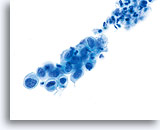

在传统的巴氏涂片上,细小的异常细胞通常会与 HSIL 相伴出现;这些细胞通常会被包裹在粘液中,或“隐藏”在背景物质内的细胞团内。由于在采用 ThinPrep 系统时,粘液和细胞碎片会经过分散处理,因此由该系统处理的标本会看起来有所不同。在使用倍镜读片时,细小的 HSIL 细胞会以单个细胞或以小细胞团的形式,在细胞的沉积背景中“凸显”出来。这些细胞应能提醒您:应更加密切地关注所呈现出的细胞物质,并查找是否有更多可供诊断的高度上皮细胞团。只要在低倍镜下看到这些细小的单个细胞或细胞团,就可在高倍镜下对这一部分玻片进行“筛查”。ThinPrep 系统的分散处理流程不会使真正的上皮细胞团发生破碎(因为高度病变存在异型性),并将会呈现出更多的单个细胞,注意到这点是至关重要的;这些是寻找病变细胞的“线索”。